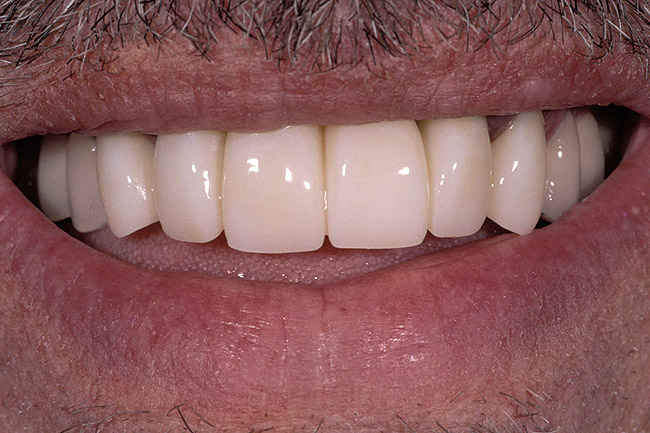

Figure 10  The final restorations demonstrate the esthetic and functional changes from lengthening the incisal edges and raising the gingiva.

Figure 10

There are several methods for identifying the correct incisal edge position pre-surgically, including the use of an overlay matrix, altering the contour of the existing teeth using reshaping or bonding, and preparing the teeth and placing temporaries.15 The patient who almost always requires tooth preparation and temporaries in order to correctly identify the incisal edge position is the one with severe wear and a need for the addition of significant length to the incisal edge of the existing teeth. Because there are such significant functional concerns in altering the incisal edge position of these patients, using a simple removable overlay to identify the esthetic position of the incisal edge and gingiva is risky. Instead, it is much more predictable to lengthen the teeth temporarily to evaluate the esthetic and functional success of the new incisal edge position prior to any crown lengthening. If the teeth are amenable to direct bonding to alter incisal edge position, this is often the best approach to temporization. If, on the other hand, the teeth are severely worn and bonding is not realistic, it will probably be necessary to prepare them and place temporaries to evaluate the change. Once it becomes clear that the new incisal edge position is acceptable both esthetically and functionally, the periodontal surgery can be completed to correct gingival levels and, therefore, crown length (Figure 6, Figure 7, Figure 8, Figure 9 and Figure 10).